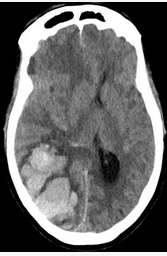

A 45-year-old woman with a medical history of hypertension presents with the acute onset of loss of consciousness and left hemiparesis. She undergoes intubation in the field for poor airway protection. A CT scan obtained at admission is shown (Figure 1). The CT scan showed no extension of the hemorrhage into the ventricular system. On examination, she has a BP of 190/100 mm Hg, heart rate of 70/min, respiratory rate of 12/min with pressure-control ventilation, and a temperature of 37.9 °C.

The treatment of intraparenchymal hemorrhage has been limited for decades to management of acute hypertension, reversal of anticoagulation (not an issue in this patient), and supportive care. Previous studies investigating hemorrhage evacuation have failed to show benefit, partly because of the destructive nature of open intracranial surgery and the methodological problems in the studies. Subset analysis of a large multinational randomized trial in the 1990s showed a trend toward benefit by using minimally invasive techniques of hemorrhage evacuation. A trial of catheter placement into the hemorrhage followed by instillation of tissue plasminogen activator (MISTIE III) failed to meet the prespecified end points but showed that patients with the most complete evacuations improved more than did those with less evacuation. The ENRICH trial showed that minimally invasive evacuation of lobar hemorrhages (between the basal ganglia and cortex in the subcortical white matter) and intraparenchymal hemorrhages improves outcome in patients (choice D is correct). Of note, cerebellar hemorrhages are often treated surgically with either decompressive suboccipital craniotomy or hemorrhage evacuation, and these were excluded from this trial.